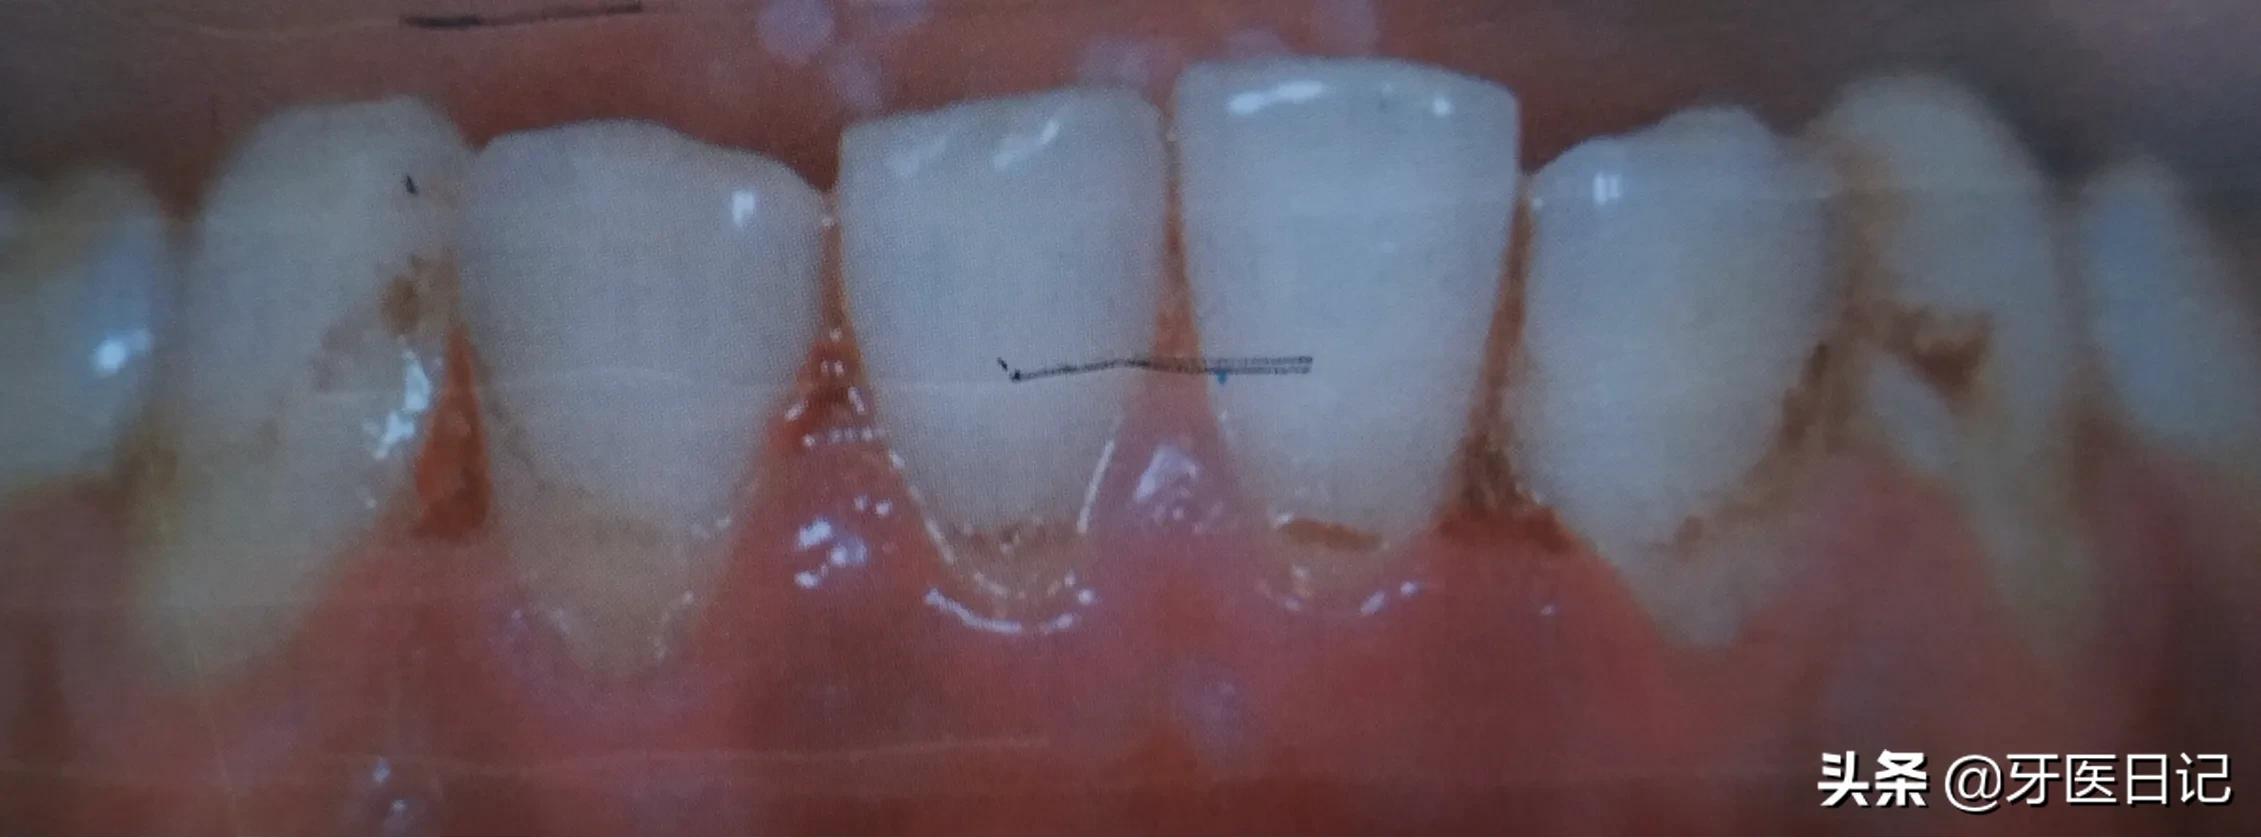

③坏死性龈口炎:发生在牙龈的急性炎症和坏死,多发生在青壮年,男性吸烟者多见,牙龈极易出血,疼痛明显,有典型的口臭

坏死性龈口炎是如何发生的呢?

患者抵抗力低下时特有细菌的毒力完成坏死性龈口炎,吸烟患者可使牙龈小血管收缩,影响牙龈局部的血流,这些都会加重牙龈的病变,同时精神紧张,睡眠不足,过度劳累也可引发本病。